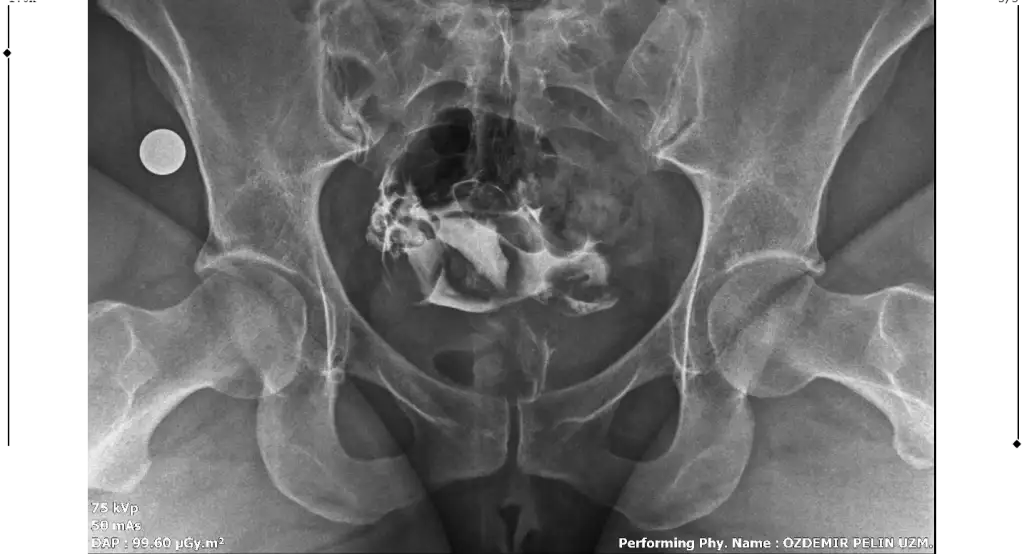

Merhaba, sağlıklı rahim gorseli ile kiyaslaninca sanki üstten biraz basık ama endişelenmeyin benim direk Y di belki çekim açısından olabilir, sizde sadece tüpleri anlayamadim dağılmış sanki açık tikaniklikda yok gibiMerhaba benim rahim filmim bu şekilde bir rapor oluşturulmadı filmi bugün çekildim doktora da gosteremedim. Yorumlanabilir misiniz?

Çok teşekkür ederim cevabınız içinMerhaba, sağlıklı rahim gorseli ile kiyaslaninca sanki üstten biraz basık ama endişelenmeyin benim direk Y di belki çekim açısından olabilir, sizde sadece tüpleri anlayamadim dağılmış sanki açık tikaniklikda yok gibi

Sizin yorumunuzu görünce bende hidrospenks baktım da sanki sağ tarafta boğum var gibi ama tek tüple de gebelik oluşuyor zaten benimde tıkalı malesef, yinede endişelenmeyin sakın korkuyorumda yorum yaparken yanlış anlaşılırim üzerim diyeGenişleme olabileceği söylendi yani sıvı olabilir dendi. Hidrosalpenks oluyor o var gibi geldi sanki bana

Anlayışınız için çok teşekkür ederim. Bakalım doktora gösterince net sonucu öğrenirim. Çok teşekkür ederim tekrardan.Sizin yorumunuzu görünce bende hidrospenks baktım da sanki sağ tarafta boğum var gibi ama tek tüple de gebelik oluşuyor zaten benimde tıkalı malesef, yinede endişelenmeyin sakın korkuyorumda yorum yaparken yanlış anlaşılırim üzerim diye

Ben de geçen hafta çektirdim HSG filmi. Raporum bugün oluştu ama anladığım kadarıyla sağ tüp açık sol tüp kapalı sanırım. Bana da yorumlama konusunda yardımcı olabilir misiniz? 4 senelik evliyim ve bebek sahibi olamadık, gebelik de hiç oluşmadı. Pcos'tan mustaribim. Tavsiyelerinizi alabilirim.

Merhaba bana da hidroselpenks gibi geldi çok hafif boğum var doktorunuzun yorumu ne oldu acabaMerhaba benim rahim filmim bu şekilde bir rapor oluşturulmadı filmi bugün çekildim doktora da gosteremedim. Yorumlanabilir misiniz?

Canım rahim yapısı güzelmişT tubiikk Ekledim görüntüleri, teşekkür ederim.

Sağ tüpün açık sol tüpün kapalıymış ben öyle anladım görüntüde de biri kapalı gözüküyor zaten